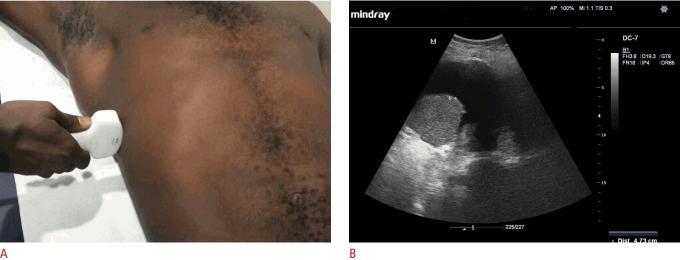

In 32 consecutive patients with clinically diagnosed pleural effusion, an ultrasound estimation was made of the volume of effusion using four different formulae, including two in the erect position and two in the supine position. Closed-tube thoracostomy drainage using a 28-Fr chest tube was performed. The total drainage was calculated after confirmation of full lung re-expansion and complete drainage by plain chest radiographs and ultrasound. The ultrasonographically estimated volume was compared to the actual total volume drained as the gold standard.

方法